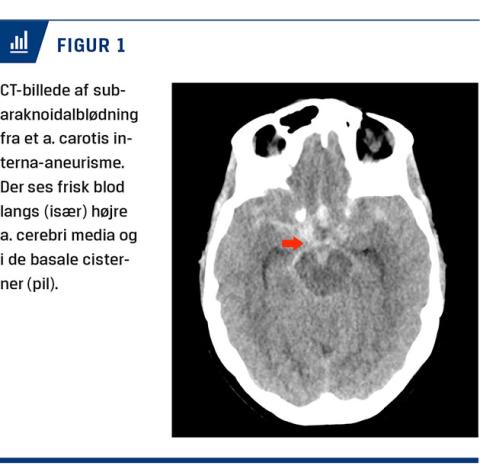

Ved mistanke om SAH udføres der en akut CT uden kontrast af cerebrum (Figur 1). Hvis denne ikke viser blod i subaraknoidalrummet, foretages der lumbalpunktur 12 timer efter formodet ictus med henblik på undersøgelse af cerebrospinalvæsken for nedbrydningsprodukter fra hæmoglobin [8]. Tidligere blev lumbalpunktur visuelt inspiceret for gulfarvning, xantokromi, men nu analyseres prøverne bl.a. for niveauet af bilirubin, oxyhæmoglobin og erytrocytter samt forholdet mellem dem. I tilfælde, hvor SAH bekræftes, foretages der CT-angiografi (CTA), hvor hjernens blodkar visualiseres med henblik på at identificere en blødningskilde, som i 80-85% af tilfældene er et rumperet aneurisme [8]. CTA har en sensitivitet på 77-97% og en specificitet på 87-100%. Hvis anamnese, CT og den kliniske tilstand taler for aneurismal SAH (aSAH), men CTA er negativ, udføres der som oftest en digital subtraktionsangiografi (DSA), som har den højeste diagnostiske værdi [12]; hvis denne er negativ, og der ikke kun foreligger en perimesencefal blødning, gentages CTA eller DSA efter ca. 14 dage, da et lille aneurisme kan være midlertidigt okkluderet af en trombe på tidspunktet for første angiografi, hvorfor undersøgelsen kan være falsk negativ i den tidlige fase [8]. Den indledende CTA kan udføres på det modtagende sygehus, men som hovedregel vil påvisning af blod i subaraknoidalrummet ved CT eller fund af hæmoglobinderivater i cerebrospinalvæsken indicere overflytning til et neurocenter, hvor undersøgelsen kan foretages. Mens udredningen pågår, skal patienten forblive indlagt og monitoreres tæt (Figur 2).